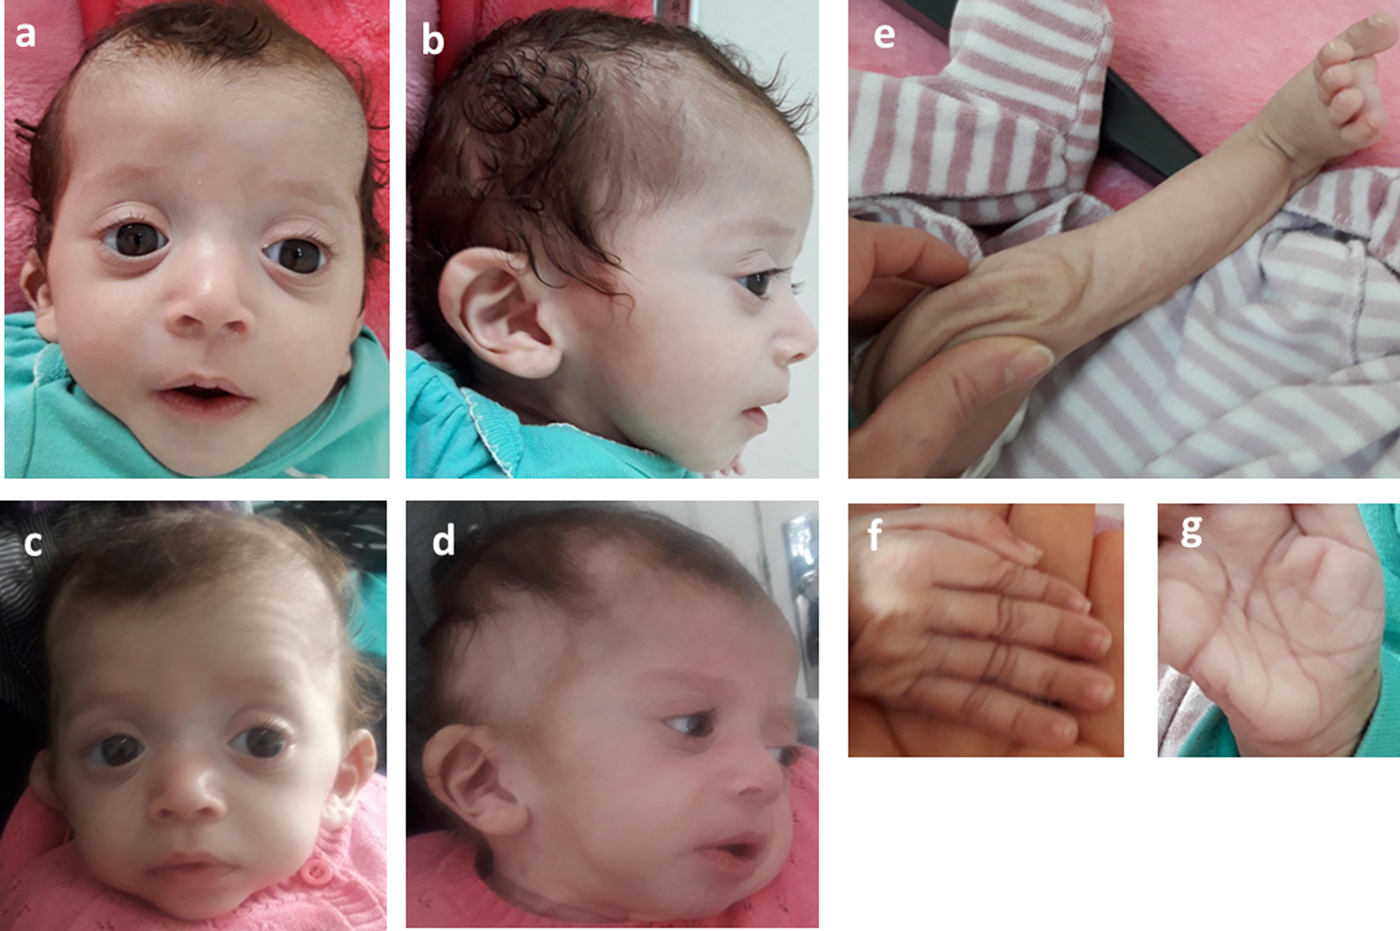

Consequently, the girl was referred to a pediatric and metabolic department for further investigations. Clinical evaluation by pediatricians and geneticists found a severe failure to thrive (Table 1). The dysmorphic facial features including large forehead, frontal bossing, bitemporal narrowing, shallow orbital ridge, hypertelorism, exophthalmos, down-slanting palpebral fissures, depressed root of nose and moderate bulbous tip, anteverted nares, low-set, posteriorly rotated ears with thickened helix, smooth long philtrum, small mouth, thin lips, retrognathia and a short neck with excess nuchal skin (Figure 2). Cutaneous abnormalities were remarkable including sparse hair, eyebrows and eyelashes, redundant and loose skin on body members, hands and feet, and deep palmoplantar creases (Figure 2). A pectus excavatum and umbilical hernia were also noted. Heart auscultation indicated systolic murmur without features of heart failure. Neurologic examination showed axial and peripheral hypertonia with large joint stiffness. Metabolic investigations (lactate cycle, plasma free and total carnitine levels, chromatographic analysis of amino acids and organic acids) were normal. The patient was diagnosed with Noonan syndrome or CFC, as key features of these syndromes were present, namely the characteristic facies, the failure to thrive, the HCM, the pectus excavatum and the cutaneous abnormalities. Molecular testing for a germline RASopathy was indicated.

Fig. 2. Photographs of the patient at 5 months (a, b, e, f, g) and 6 months (c, d): note the dysmorphic facial features (a, b, c, d) including large forehead, frontal bossing, bitemporal narrowing, shallow orbital ridge, hypertelorism, exophthalmos, down-slanting palpebral fissures, depressed root of nose and bulbous tip, anteverted nares, low-set, posteriorly rotated ears with thickened helix (b, d), smooth long philtrum (a) becoming deeply grooved (c), small mouth, thickening of lips (c), full cheeks (c) and retrognathia (b, d) and the cutaneous abnormalities including sparse hair, eyebrows and eyelashes (a, b, c, d), redundant and loose skin on body members (e), hands and feet (f), and deep palmoplantar creases (g).

At the age of 6 months, at blood sampling, the patient showed some changes in facial appearance; the philtrum became deeply grooved, the lips thicker, the nose bulbous and the cheeks full, which were most suggestive of Noonan syndrome (Figure 2).